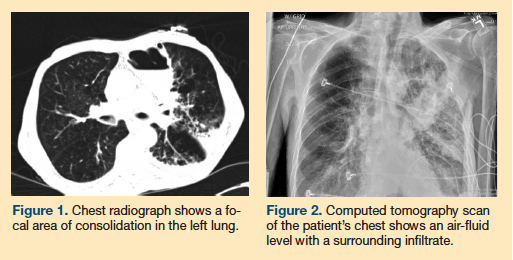

His initial vital signs were significant for a heart rate of 105 beats per minute, blood pressure of 104/76 mm Hg, and an oxygen saturation level of 93% on room air. Significant physical examination findings included cachexia and a sacral ulcer. His lungs showed vesicular breath sounds with crackles in the left upper lobe. Laboratory values indicated no leukocytosis, and his electrolyte panel, blood urea nitrogen level, and creatinine level were all within normal limits. A radiograph (Figure 1) and computed tomography (CT) scan of his chest (Figure 2) showed significant findings.

Based on the patient’s clinical history and radiological findings, a diagnosis of an infected emphysematous bulla was made. A lung bulla is an air-filled space that occurs after destruction of the alveoli, specifically a rupture of the alveolar septum.1 An infected emphysematous bulla is an uncommon complication of COPD. The literature is limited to case reports and case series, many of which were published before 2000. In most of the cases described in the literature, the diagnosis is made based on the patients’ clinical history of pleuritic chest pain and constitutional signs of infection, along with a chest radiograph showing an air-fluid level contained within a bulla.2-4 Many patients also present with cough. The presence of a bulla in the same location on a prior chest radiograph strengthens the diagnosis.4-6 The differential diagnosis is broad, and it includes lung abscess, hemorrhagic bulla, granulomatous disease, tuberculosis, necrotizing pneumonia, congestive heart failure, and malignancy. We discuss several of these diagnoses later in the article.